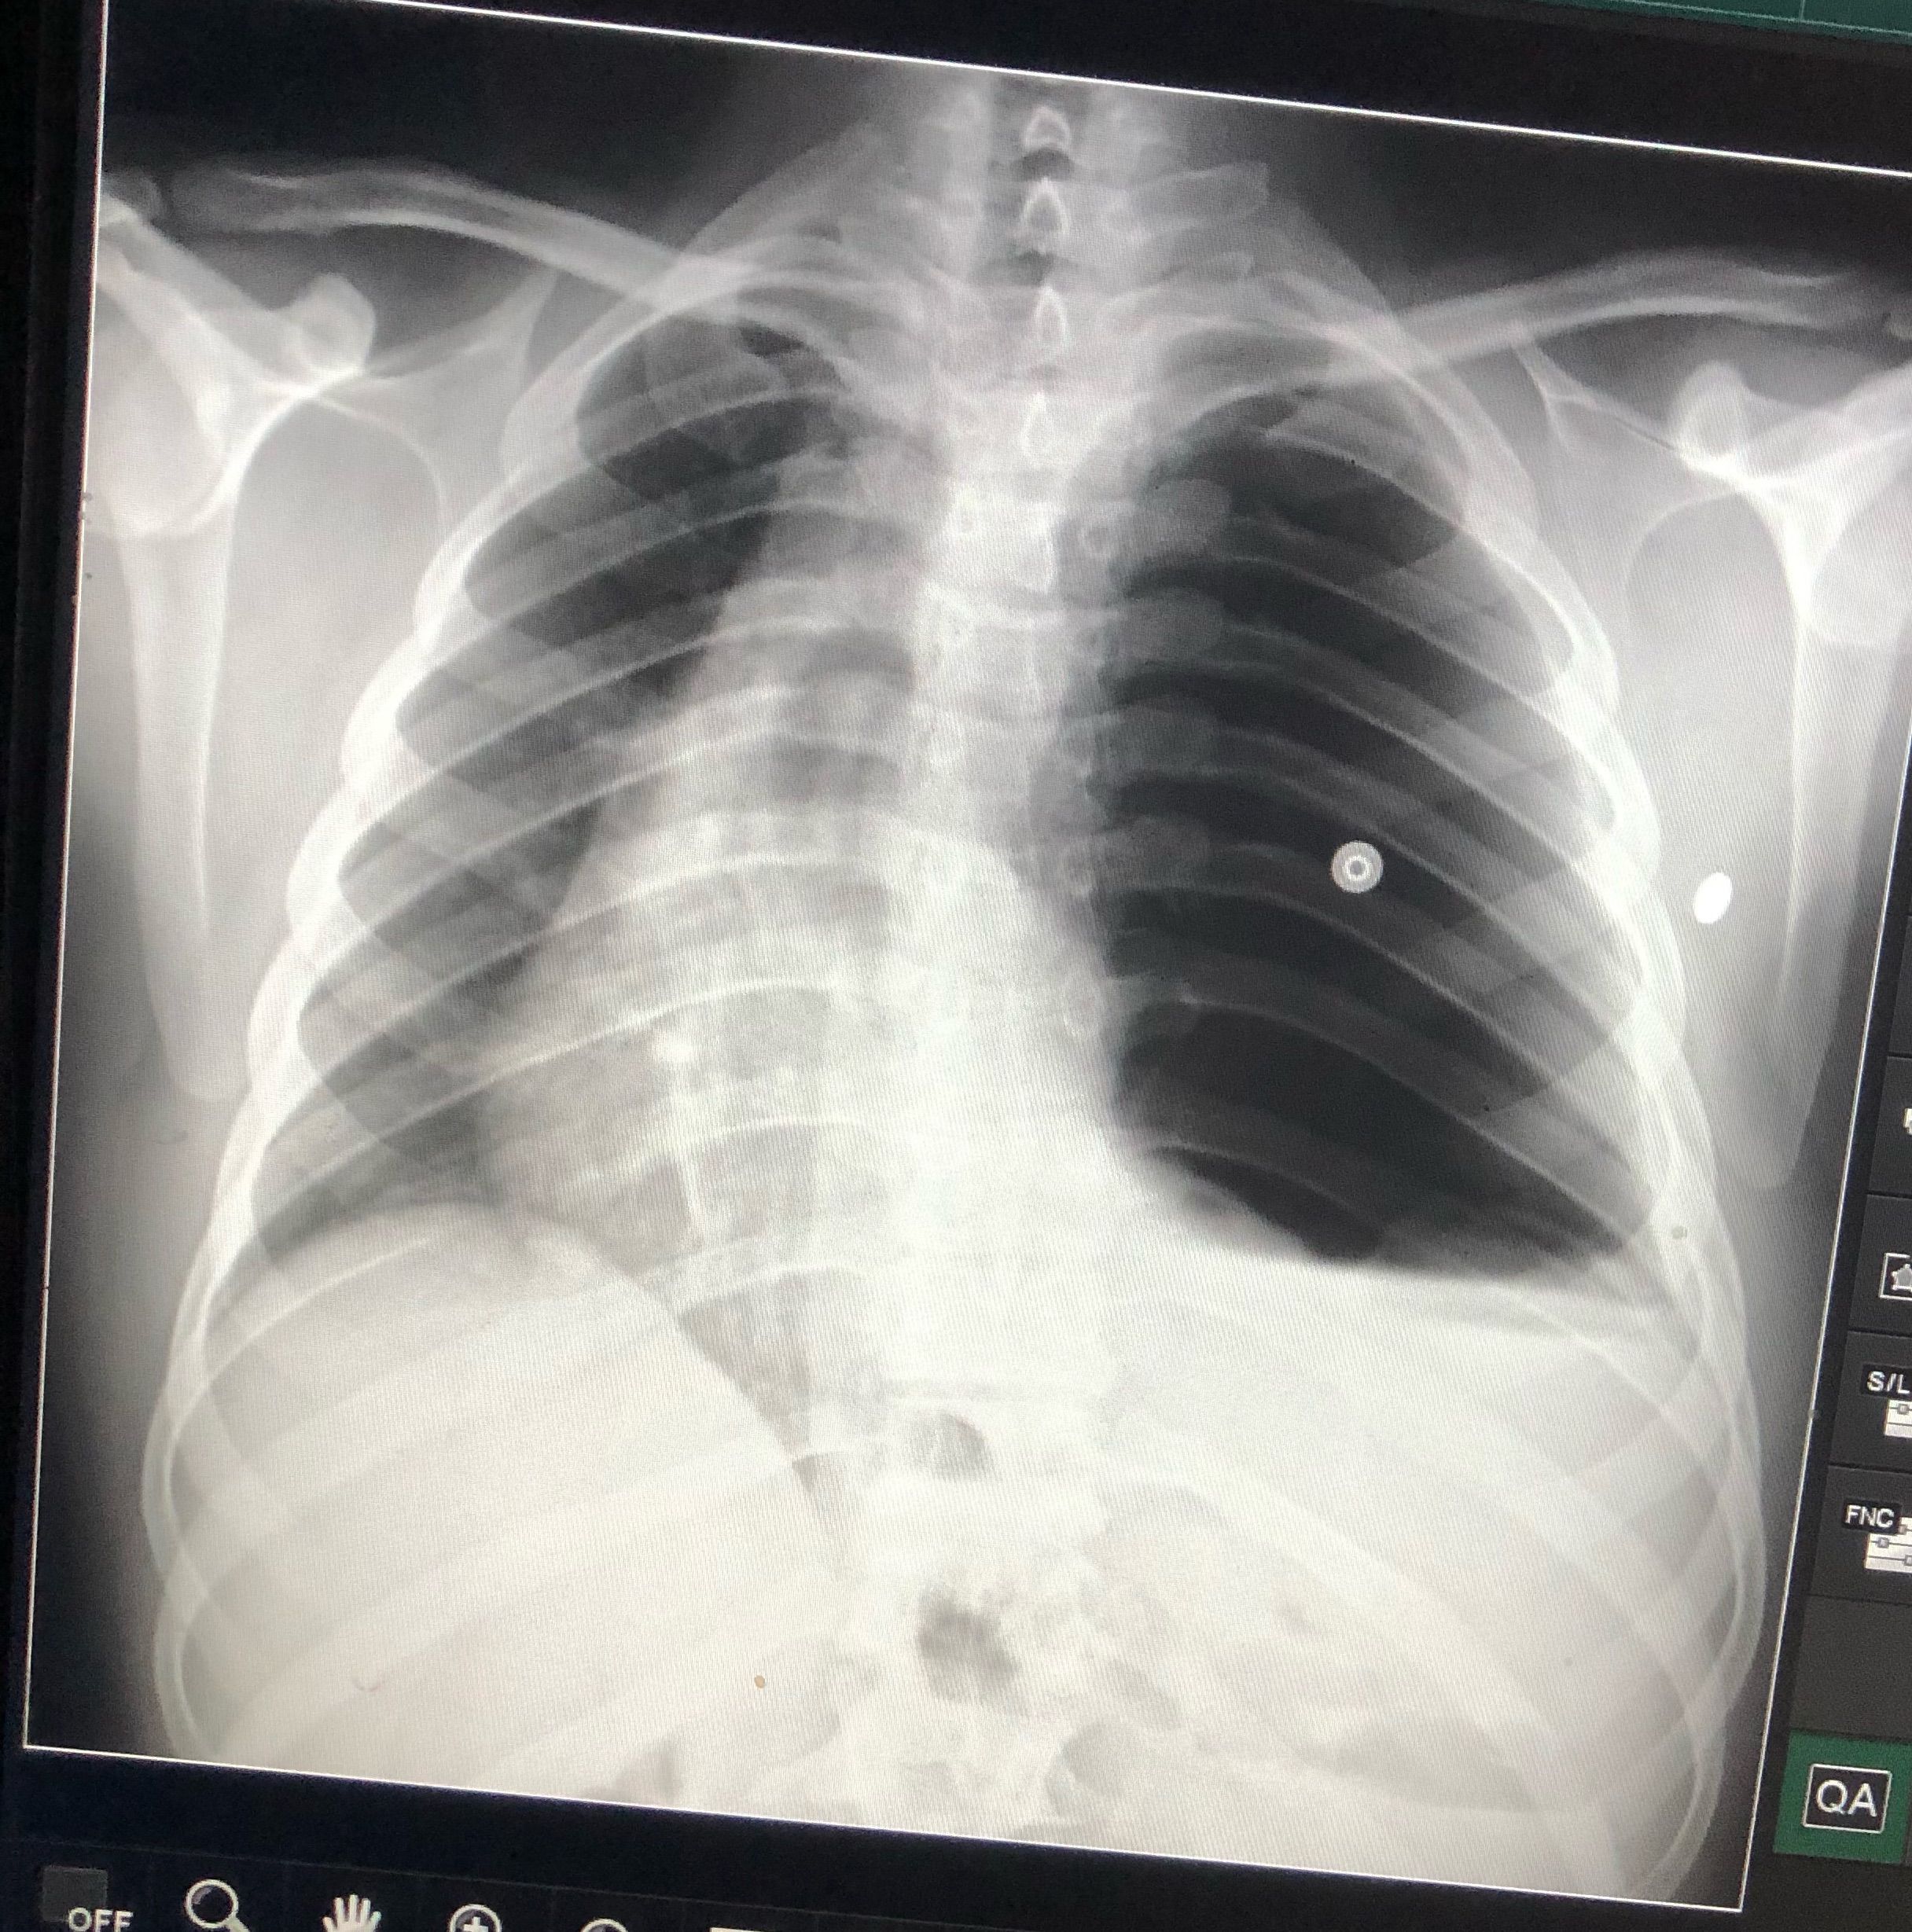

A case of hydropneumothorax

This patient has cough , dyspnea since 12/6/2021 presented to Emergency hospital 1/7/2021 , o2saturation was 94 pulse was150 Bp 120/70 , how to manage?